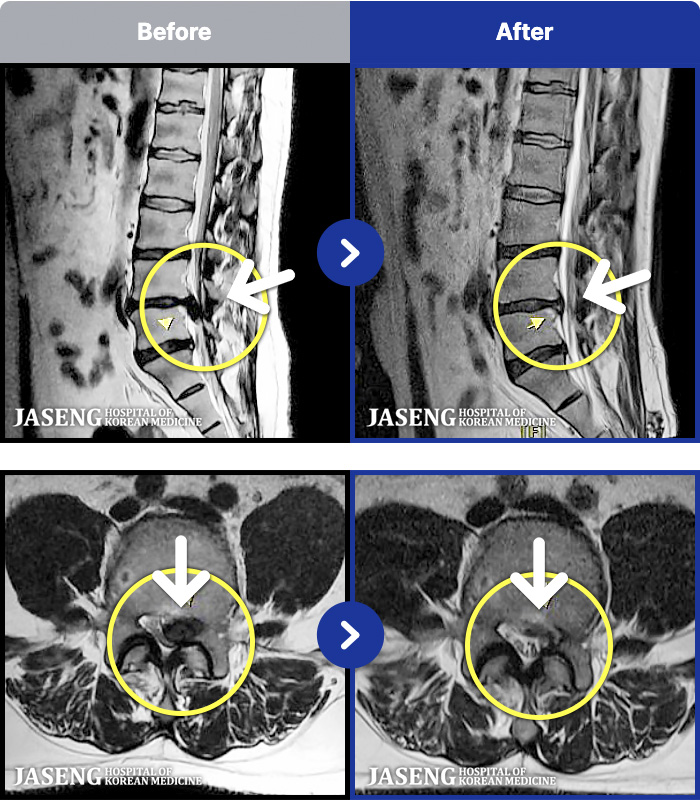

1,240 MRI ũ ʸ Ȯϼ.

MRI ġ

㸮 ϻ .